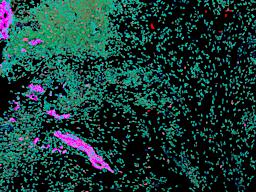

Pancreatic ductal adenocarcinoma is a lethal disease with limited treatment options and poor survival. We studied 83 spatial samples from 31 patients (11 treatment-naïve and 20 treated) using single-cell/nucleus RNA sequencing, bulk-proteogenomics, spatial transcriptomics and cellular imaging. Subpopulations of tumor cells exhibited signatures of proliferation, KRAS signaling, cell stress and epithelial-to-mesenchymal transition. Mapping mutations and copy number events distinguished tumor populations from normal and transitional cells, including acinar-to-ductal metaplasia and pancreatic intraepithelial neoplasia. Pathology-assisted deconvolution of spatial transcriptomic data identified tumor and transitional subpopulations with distinct histological features. We showed coordinated expression of TIGIT in exhausted and regulatory T cells and Nectin in tumor cells. Chemo-resistant samples contain a threefold enrichment of inflammatory cancer-associated fibroblasts that upregulate metallothioneins. Our study reveals a deeper understanding of the intricate substructure of pancreatic ductal adenocarcinoma tumors that could help improve therapy for patients with this disease.